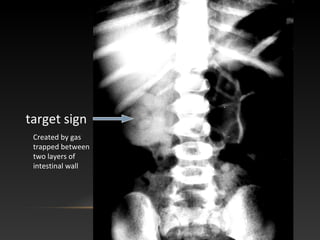

•Radiographic signs of Intussusception:

target sign

crescent sign

absent liver edge sign (also called absence of the subhepatic angle)

bowel obstruction

May have a normal x-ray!

Where is

the target

sign?

Created by gas

trapped between

two layers of

intestinal wall